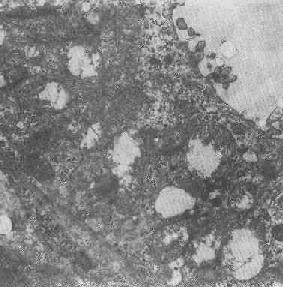

肾小管上皮细胞线粒体部分空泡变

图1-10肾小管上皮细胞线粒体部分空泡变

2.大小改变 细胞损伤时最常见的改变为线粒体肿大。根据线粒体的受累部位可分为基质型肿胀和嵴型肿胀二种类型,而以前者为常见。基质型肿胀时线粒体变大变圆,基质变浅、嵴变短变少甚至消失(图1-9)。在极度肿胀时,线粒体可转化为小空泡状结构(图1-10,图1-11)。此型肿胀为细胞水肿的部分改变。光学显微镜下所谓的浊肿细胞中所见的细颗粒即肿大的线粒体。嵴型肿较少见,此时的肿胀局限于嵴内隙,使扁平的嵴变成烧瓶状乃至空泡状,而基质则更显得致密。嵴型肿胀一般为可复性,但当膜的损伤加重时,可经过混合型而过渡为基质型。